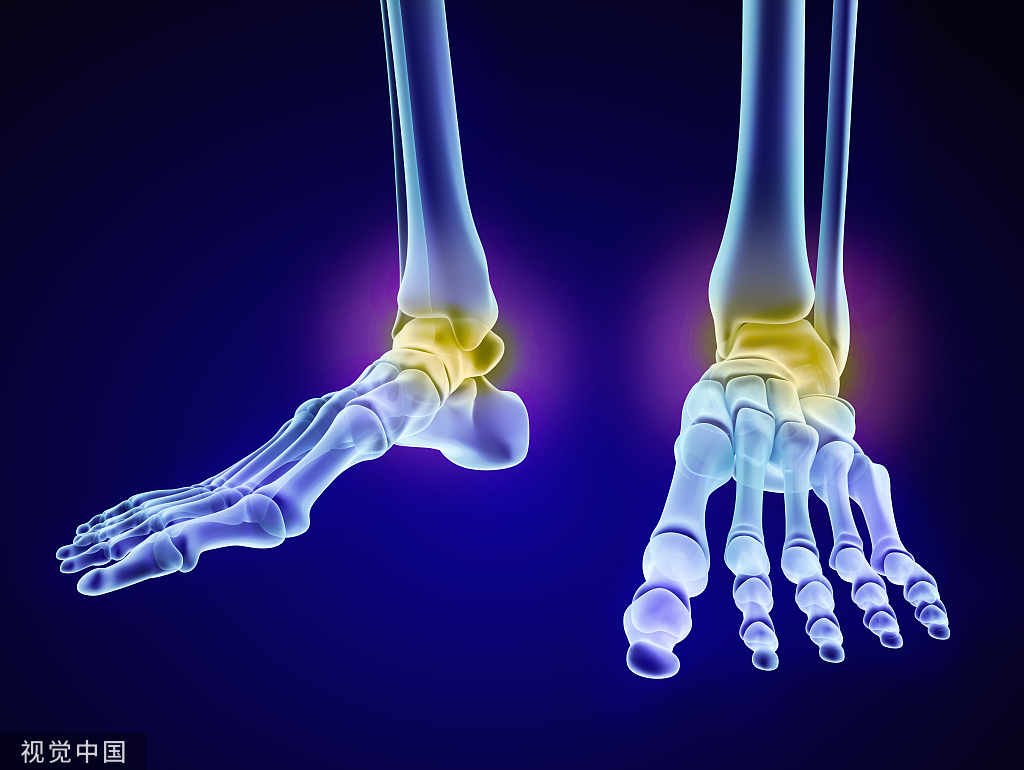

下肢牵引术应用比较广泛,从股骨颈骨折,转子间骨折,股骨骨折,到胫腓骨骨折等,都需要用到牵引。对于下肢骨折,两种牵引方法均可应用:皮牵引用于临时固定或术前稳定;而骨牵引多用于手术禁忌患者的治疗性措施。

Buck's(图 7)或 Russell's(图 8)皮肤牵引:在股骨骨折,转子间骨折或髋部骨折中应用广泛,下肢骨折使用皮牵引一般不能达到复位效果,但是可以在一定程度上减轻疼痛和保持局部肢体长度。